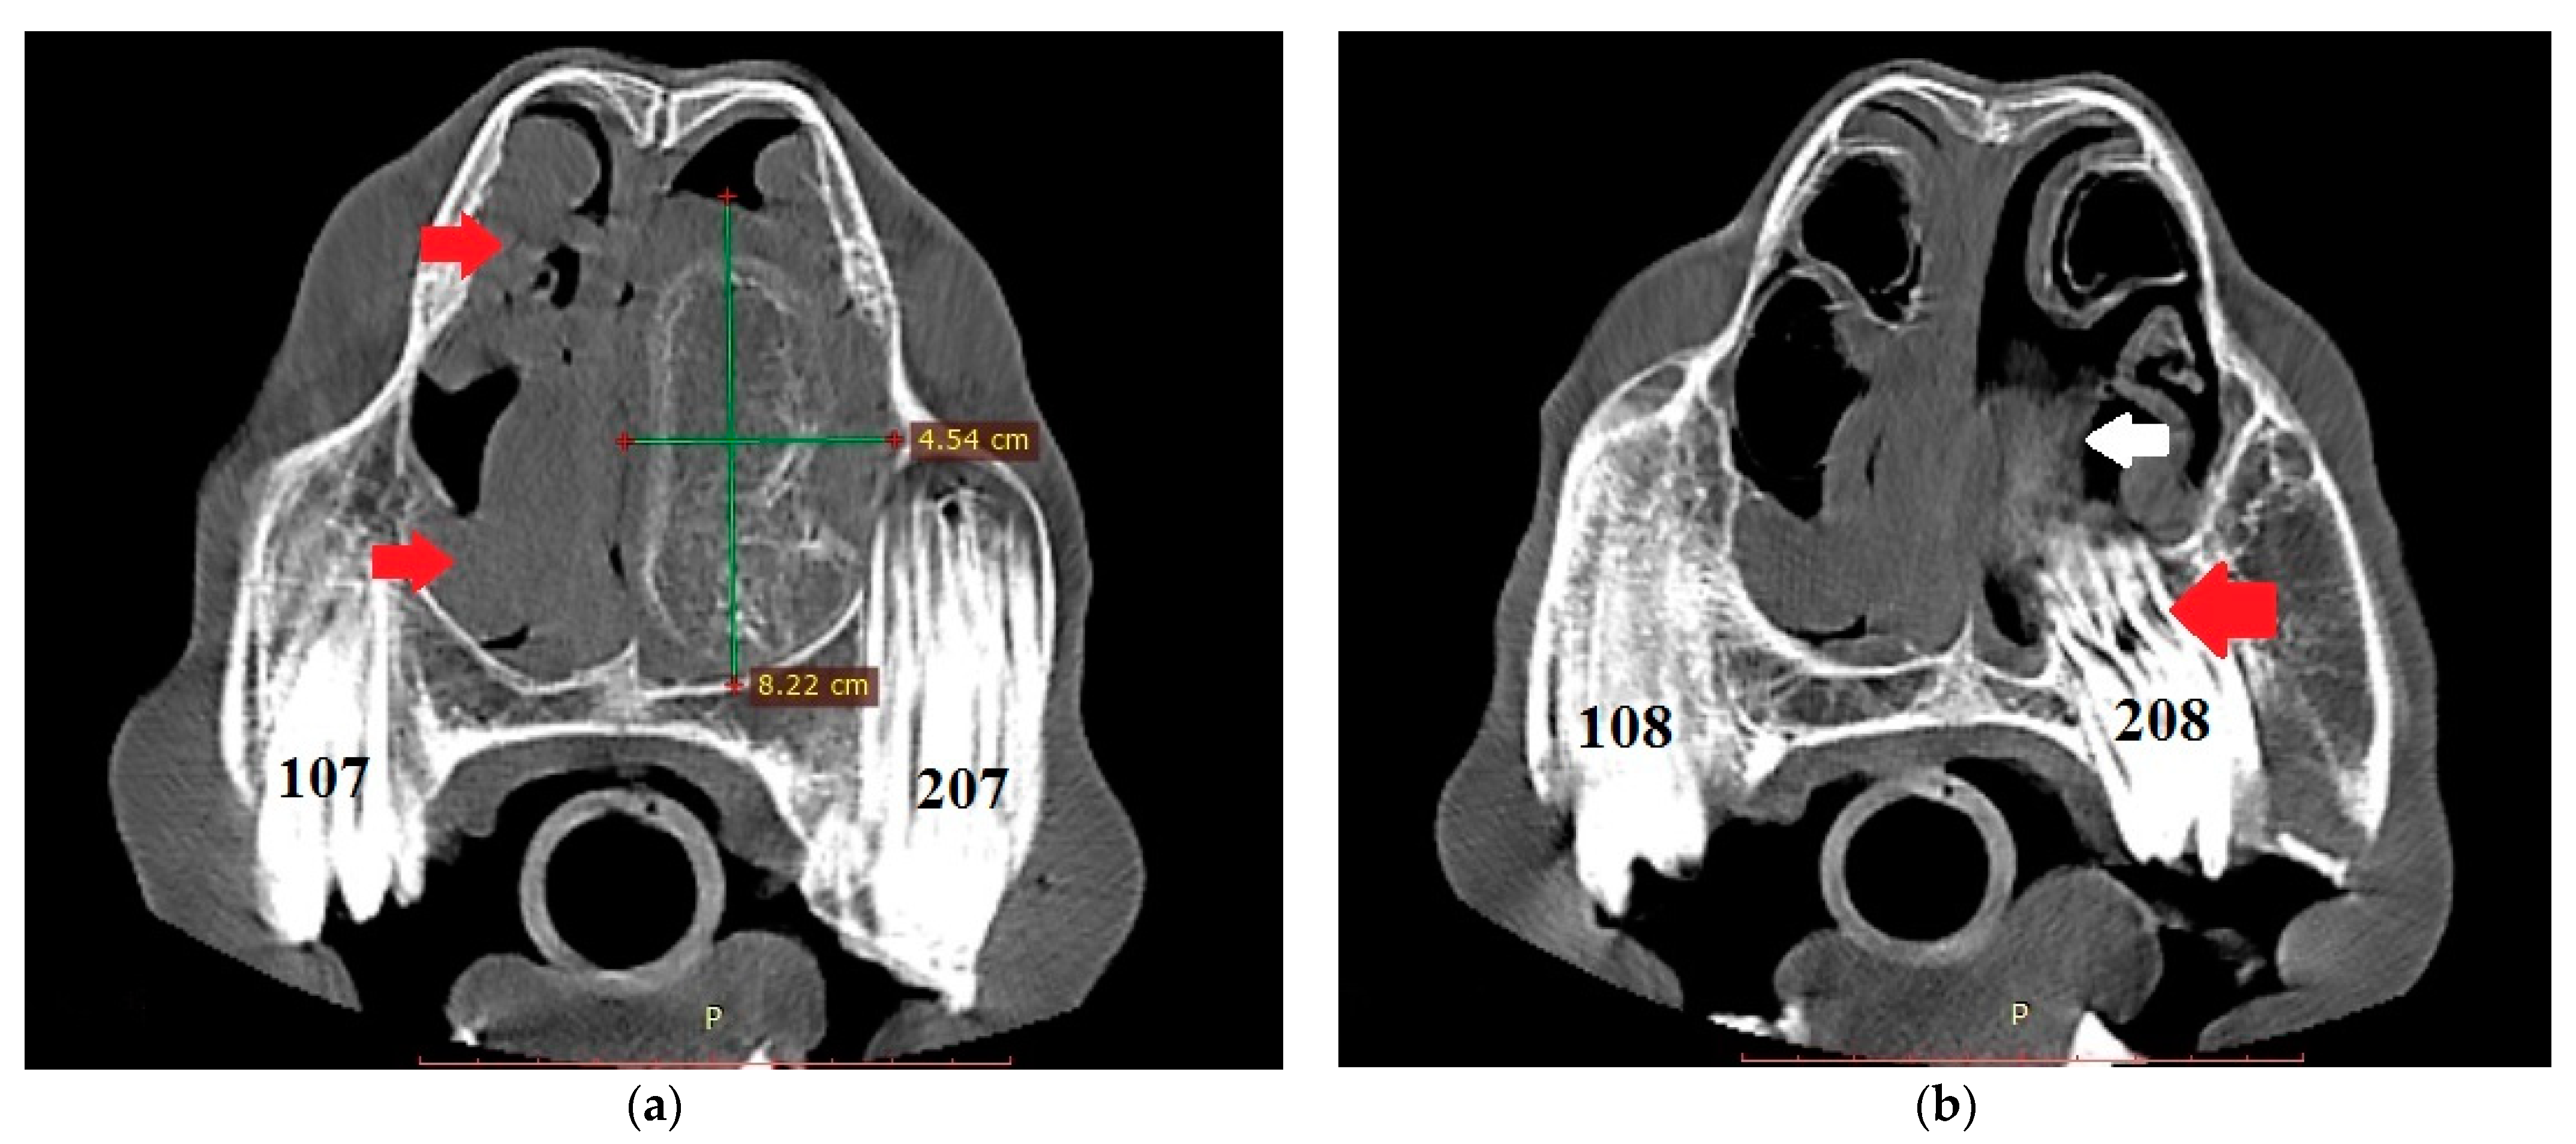

The endoscopic examination of the right nostril revealed the rightward bending of the nasal septum; an examination of the left side was unavailable due to the presence of the mass. Computed tomography of the head was performed under general anesthesia in dorsal recumbency. The patient was sedated with detomidine (0.02 mg/kg) prior to anesthetic induction with diazepam (0.1 mg/kg) and ketamine (2.2 mg/kg). Anesthesia was maintained using isoflurane (induction 5%, maintenance 2–3%). CT images were acquired with a Revolution 750 CT scanner, GE Healthcare Corporation, Chicago, IL, USA (120 kV, 280 mA, at 1.3 mm slice thickness). Two-dimensional tomographic sections were viewed using the RadiAnt DICOM 2020.2.3 software. Multiplanar image reconstructions allowed for the identification of the exact location of the mass, which extended from the level of Triadan 208 to the rostral part of the nasal cavity. The space-occupying lesion was well defined, heterogeneous, and measured approximately 22 × 9 × 5 cm (length × height × width) with internal zones of calcification (Figure 3). The mass caused the deformation and compression of the left dorsal and ventral nasal conchae, the deviation of the nasal septum, and the thickening of the right dorsal and ventral nasal conchae (Figure 4a). The tooth was displaced palatally to the nasal cavity, and the morphology was abnormal due to hypoplastic reserve, clinical crown and roots, enlarged infundibula, and variable radiodensity. The apex of 208 was deformed and had a direct connection to the mass (Figure 4b). The sinuses appeared normal.

Figure 4.

(a) Transverse CT image at the level of Triadan 07 (bone algorithm, WW1500, WL 300), demonstrating a heterogeneous mass obliterating the left nasal cavity (width × height—green lines). Note the rightward deviation of the nasal septum and thickened right dorsal and ventral nasal conchae (red arrows). Internal zones of calcification are present. (b) CT transverse plane at the level of Triadan 08 (bone algorithm, WW1500, WL 300). Note the relationship of the mass (white arrow) with the dental apex of Triadan 08 (red arrow).